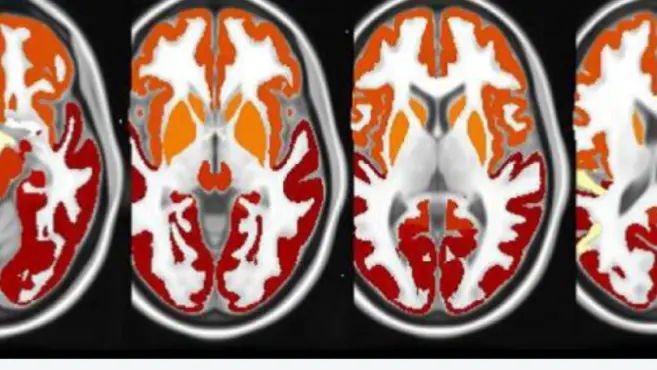

Volumetric MRI

IXICO hails the introduction of IXIQ.Ai, its new brain imaging technology

Revolutionizing Analytics: The Role of Deep-Learning AI in CNS Clinical Trials

AD/PD 2021 Poster - Automatic segmentation using deep learning for the hippocampus

A deep-learning based framework for brain-atrophy measurement - AD/PD 2021

Using AI To Advance Imaging Operations & Analysis in Phase III Clinical Trials for Alzheimer’s